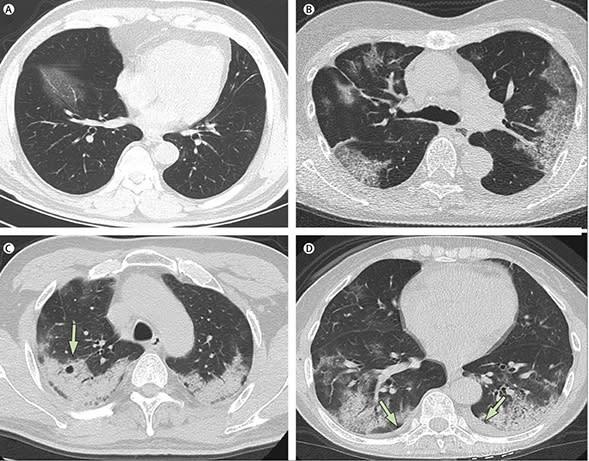

“Phổi trắng” là chỉ bệnh nhân bị viêm phổi nặng khi kiểm tra X-quang, phổi xuất hiện một mảng trắng lớn, có nghĩa là phổi bị ăn mòn và xơ hóa nghiêm trọng, đây là một triệu chứng nghiêm trọng của bệnh viêm phổi, gây nguy hiểm đến tính mạng người bệnh.

Ngoài các thành viên gia đình của người quá cố đăng tin về phổi trắng, còn có nhân viên y tế, những người lo lắng triệu chứng điển hình của “phổi trắng” trong đợt bùng phát dịch ở Vũ Hán 3 năm trước sẽ xuất hiện trở lại. Nhiều nhân viên y tế đã đăng trên Weibo những bức ảnh chụp trong bệnh viện cho thấy phổi của nhiều bệnh nhân đã bị xơ hoàn toàn.

“Phổi trắng” còn được gọi là Hội chứng suy hô hấp cấp tính (ARDS), thường dùng để chỉ biểu hiện của bệnh nhân bị viêm phổi nặng khi kiểm tra X-quang hoặc CT. Biểu hiện lâm sàng là tức ngực, khó thở, hô hấp kém, độ bão hòa oxy trong máu của bệnh nhân phổi trắng thấp, dẫn đến tình trạng thiếu oxy trầm trọng.